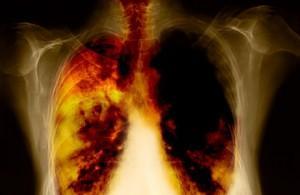

Un nuevo descubrimiento del Centro de Estudio del Cáncer de la universidad de Colorado acerca del cáncer de pulmón puede llevar a nuevos hallazgos sobre esta enfermedad.